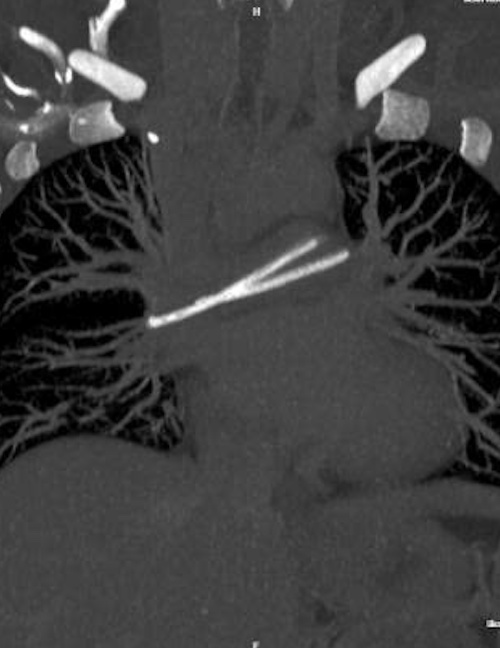

During a routine check-up at a private medical facility, a chest CT scan revealed a foreign object in her heart, stretching across the bifurcation of her pulmonary artery. A subsequent chest X-ray confirmed that the catheter had broken; the port chamber remained under her right collarbone, while the distal segment had migrated into her heart and pulmonary artery. The patient was then transferred to Hospital 175 for treatment.

Image of the foreign object on the CT scan. Photo: Hospital provided |